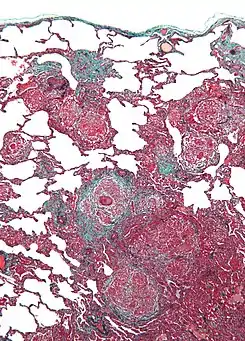

Micrografía de neumonitis por hipersensibilidad, la histología corresponde a un pulmón de cuidador de aves. Biopsia de pulmón . Tinción tricrómica.

Un diagnóstico definitivo puede ser difícil de conseguir sin una prueba invasiva, pero la exposición extensa a las aves combinada con la capacidad de difusión disminuida es fuertemente sugestiva de esta enfermedad. La radiografía o tomografía muestran cambios físicos en la estructura de pulmón (patrón de vidrio esmerilado) con el progreso de la enfermedad. La distribución precisa y los tipos de daño de tisular difieren entre enfermedades similares, al igual que la respuesta a tratamiento con prednisona. Hay dos formas de pulmón de cuidador de aves: la aguda y la crónica. El daño alveolar difuso (DAD) puede cursar con insuficiencia respiratoria aguda; la fibrosis intersticial es típica de la forma crónica.[2] En ambos, la respuesta inflamatoria subyacente se detiene tras la exclusión del alérgeno, pero los síntomas pueden persistir según el grado de daño sufrido.[2] Entre los procedimientos invasivos, lavado broncoalveolar típicamente muestra linfocitosis prominente con una proporción CD4+/CD8+ invertida, y la biopsia de pulmón normalmente revela inflamación con granulomas no necrotizantes.[2]